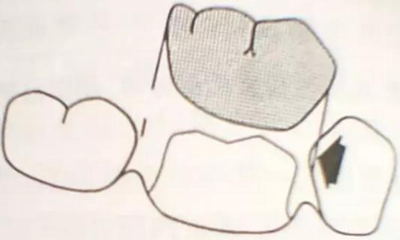

牙體各個面的解剖厚度

烤瓷牙的設(shè)計方式